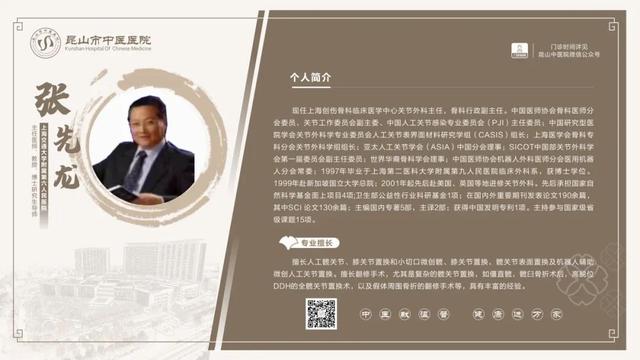

6��23��-6��29��������ר�ҳ���һ����

������鿴��ͼ���Ե���ʵ�ʳ���Ϊ��

6��23��-6��29�������dz���ר�ҽ���